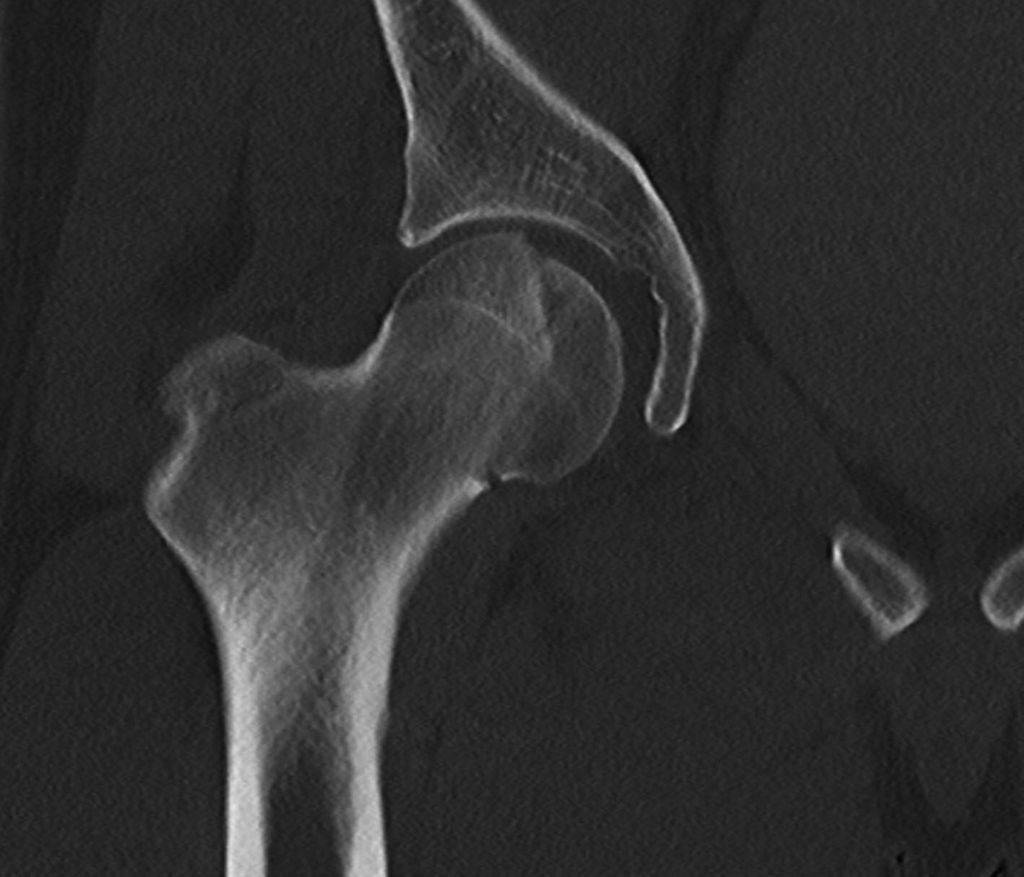

Abb. 3: Zur präoperativen Planung und zur Beurteilung des geschlossenen Repositionsergebnisses ist der Goldstandard die Computertomografie

Neben der klinischen Erstuntersuchung und Anamnese umfasst die Diagnostik die konventionelle native Röntgendiagnostik des verletzten Hüftgelenkes mit Standardaufnahmen im a.-p. und axialen Strahlengang (Abb. 1, 2) sowie gegebenenfalls die Anfertigung von Ala- und Obturatoraufnahmen. Obligatorisch empfehlen wir die Anfertigung eines Hüftübersichtsröntgens und gegebenenfalls, sofern möglich, auch eine Faux-Profil-Aufnahme. Zur präoperativen Planung und zur Beurteilung des Repositionsergebnisses ist der Goldstandard die Computertomografie (Abb. 3) mit Anfertigung einer 3D-Rekonstruktion. Im Rahmen der Notfalldiagnostik spielt die Magnetresonanz keine wesentliche Rolle. Im Hinblick auf die Diagnostik sekundär auftretender Komplikationen ist jedoch die Bedeutung des MRT unumstritten.